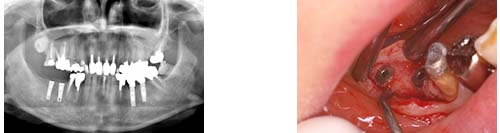

インプラント(抜歯即時埋入)

保存不可能な歯を抜歯し即時にインプラントを埋入する方法です。

前歯の根が割れてしまったために保存不可能 |

抜歯即時埋入 |